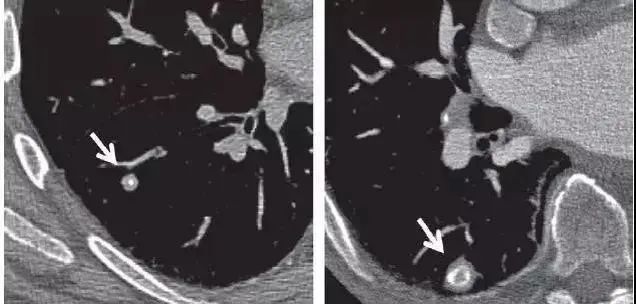

横看成岭侧成峰,下图CT扫描时显示的是叶间裂上的一个结节影(图1),而CT冠状面重建则显示该结节影其实为线状的疤痕或淋巴组织(图2)。